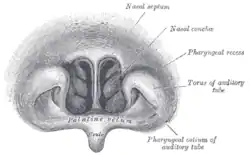

Frontalschnitt durch die Nasenhöhle

Frontalschnitt durch die Nasenhöhle -

Siehe auch nebenstehende Abbildung von Henry Vandyke Carter. Wegen der Spiegelung erkennt man in der rechten Bildhälfte die drei rechten Conchae mit ihren vier Meatus und spiegelsymmetrisch in der linken Bildhälfte die drei linken Conchae mit ihren vier Meatus.